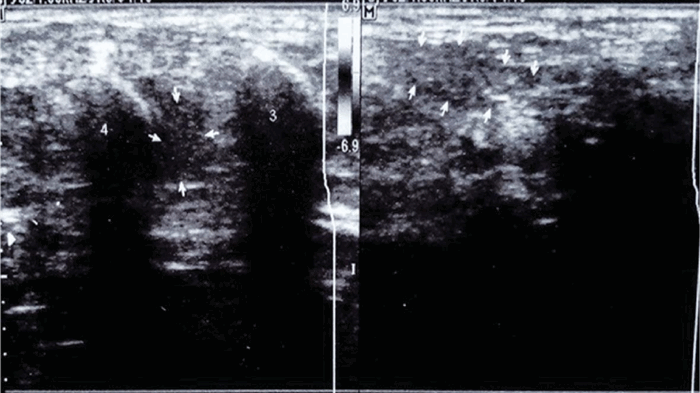

Неврома Мортона была выявлена только у 3 пациентов (2,6%), визуализировалась как гипоэхогенное образование вытянутой веретенообразной или каплевидной формы, с четкими контурами, лоцирующееся только с подошвенного доступа и строго в промежутке между головками 3-й и 4-й плюсневых костей, связанное с указанным пространством гипоэхогенным тонким тяжом. Размер образования варьировал от 37 х 41 х 75 мм до 45 х 51 х 112 мм. Режим цветового допплеровского картирования исключал васкуляризацию образований (рис. 4, 5).

Рис. 4. Солидное объемное образование, исходящее из 3-го межплюсневого промежутка, вытянутой каплевидной формы, с четким контуром, однородной структуры, гипоэхогенное, связанное с указанным пространством, тяжом. Неврома Мортона

Рис. 5. Солидное объемное образование, исходящее из 3-го межплюсневого промежутка, каплевидной формы, с четким контуром, однородной структуры, гипоэхогенное, связанное с указанным пространством тяжом. Неврома Мортона

Рисунок 1 (а, б). (а) — поперечное сканирование, лоцируется утолщение межпальцевого нерва между головками 3-й и 4-й плюсневых костей сниженной эхогенности, нормальная слоистая структура нерва не прослеживается; (б) — продольное сканирование веретенообразного утолщения межпальцевого нерва на протяжении до 2 см, оболочки нерва четко не визуализируются.

В результате проведенного исследования было выявлено наличие локального веретенообразного утолщения межпальцевого нерва между головками 3-й и 4-й плюсневых костей правой стопы на протяжении до 2 см. Утолщение представляло собой образование неоднородной гипоэхогенной структуры с нарушением нормальной слоистой структуры нервного ствола. При сканировании в продольном направлении при динамической пробе прослеживалась четкая связь имеющихся изменений с межпальцевым нервом. Мягкие ткани по тыльной поверхности этой зоны были незначительно утолщены за счет подкожного отека. При лоцировании во время проведения компрессии отмечалась значительная болезненность.